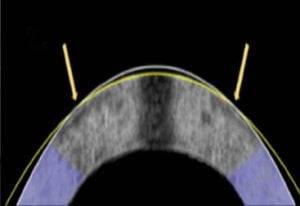

이들은 근시 교정을 위해 길쭉해진 안구를 편평하게 바꾸기 위한 백금 렌즈를 만들었다. 이후 토끼의 안구에 렌즈를 끼운 뒤 전기가 흐르도록 했고 1분이 지난 뒤 각막의 곡률은 렌즈와 같게 바뀐 것을 확인했다. 라식 수술과 소요 시간은 비슷하지만 레이저를 활용하지 않아 적은 비용이 드는 데다 절개도 필요없다고 연구진은 설명했다.

토끼 12마리를 활용해 해당 치료법을 적용한 결과 10마리의 근시를 교정하는 데 성공했다. 치료 후에도 안구 세포는 이전처럼 잘 유지되는 것도 확인했다.